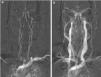

El análisis de la estenosis se basa en proyecciones de alta intensidad (MIP), que consisten en permitir un realzamiento de las estructuras que presentan una mayor intensidad de señal. La forma de las reconstrucciones de las imágenes MIP se parece a las imágenes adquiridas en las angiografías por radiología convencional6.

NASCETLos criterios que utiliza la NASCET8 son a día de hoy los más utilizados para llevar a cabo el cálculo del porcentaje de estenosis. Su cálculo se realiza en base a 2 medidas principales: la medida del diámetro a nivel de la lesión, y la medida del diámetro de la ACI distal a la lesión, donde el vaso ya ha recuperado su diámetro morfológicamente normal (fig. 8).

ECSTEste método9 también utiliza la medida del diámetro a nivel de la lesión para realizar el cálculo, pero a diferencia de la NASCET, este método sustituye la medida del diámetro de la ACI distal a la lesión por la del diámetro total del vaso a nivel de la lesión, incluyendo la placa (fig. 8).